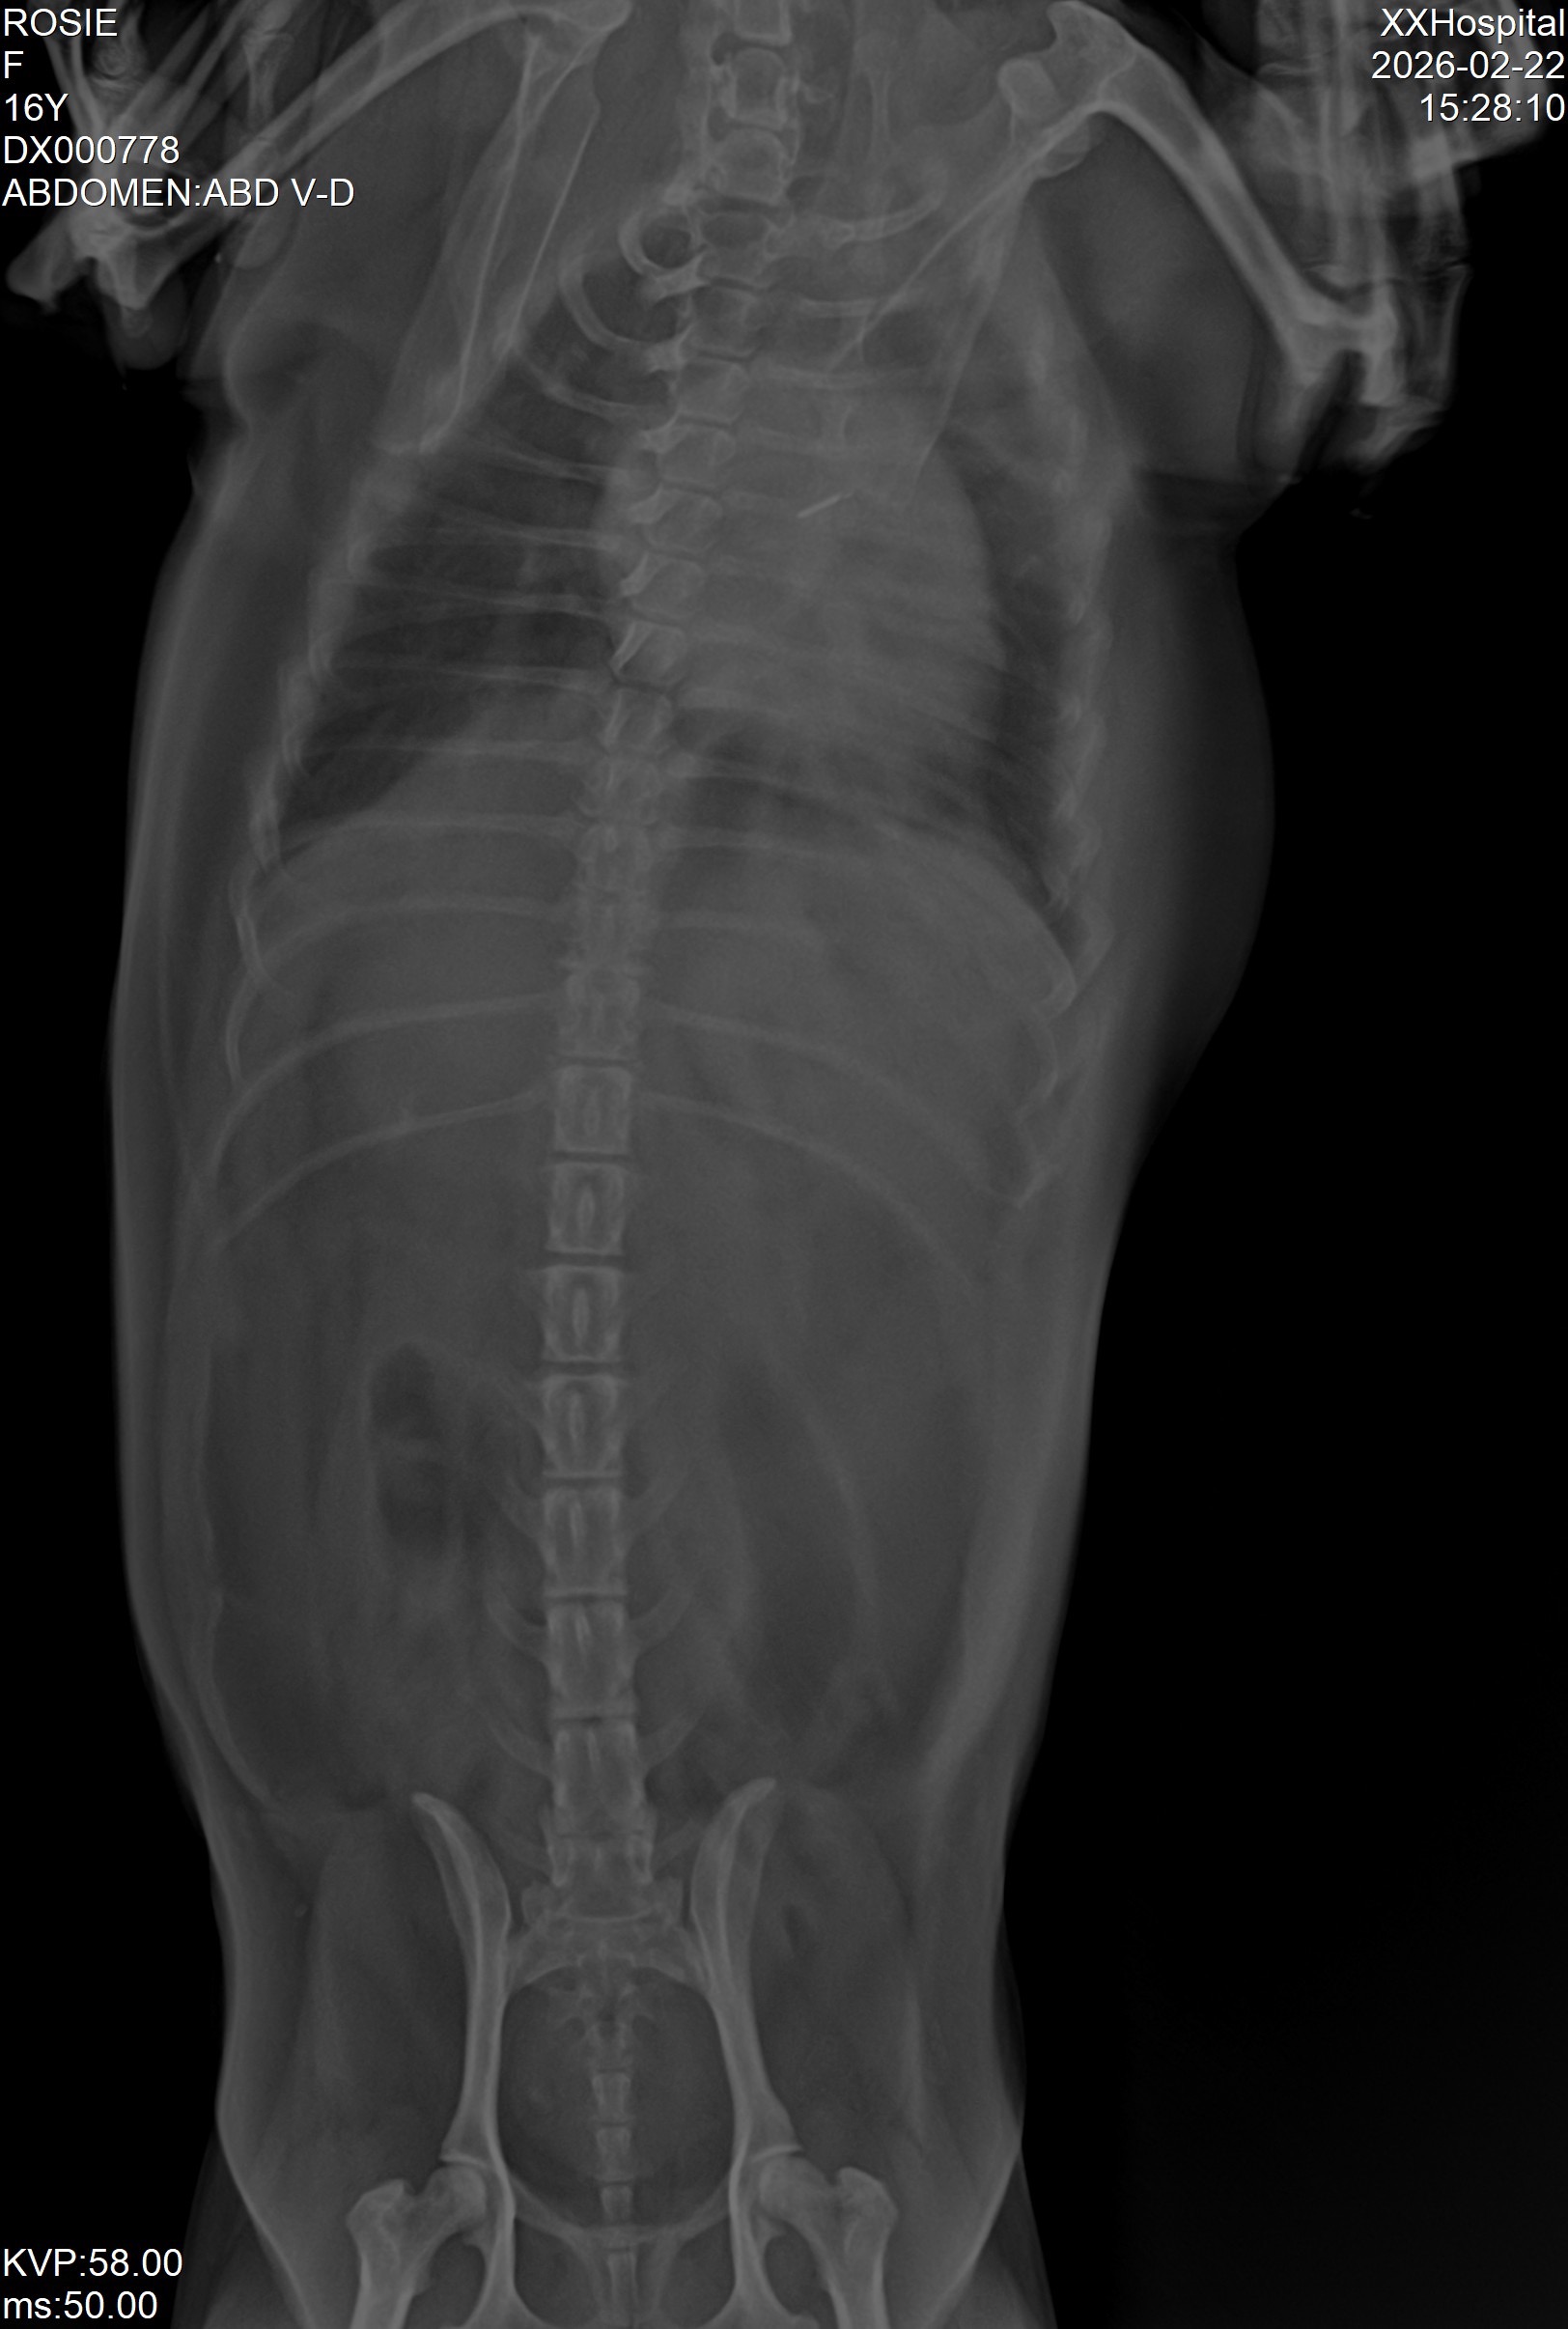

I adopted Rosie when she was 10 years old, and over the last six years, we have become completely inseparable. She is not just a pet; she is my anchor. Recently, Rosie's health took a scary turn. We had X-rays done, and the vet gave me devastating news: her heart is currently so enlarged that it is crushing one of her lungs.

I have set the fundraiser goal to $18,000 MXN to cover these specialized diagnostics, the extra vet visits we've had to make, her prescription food, and to provide a safety net for the expensive heart medications she must now take daily. I have uploaded her estimates, bloodwork, and X-rays showing her enlarged heart to this page for full transparency.